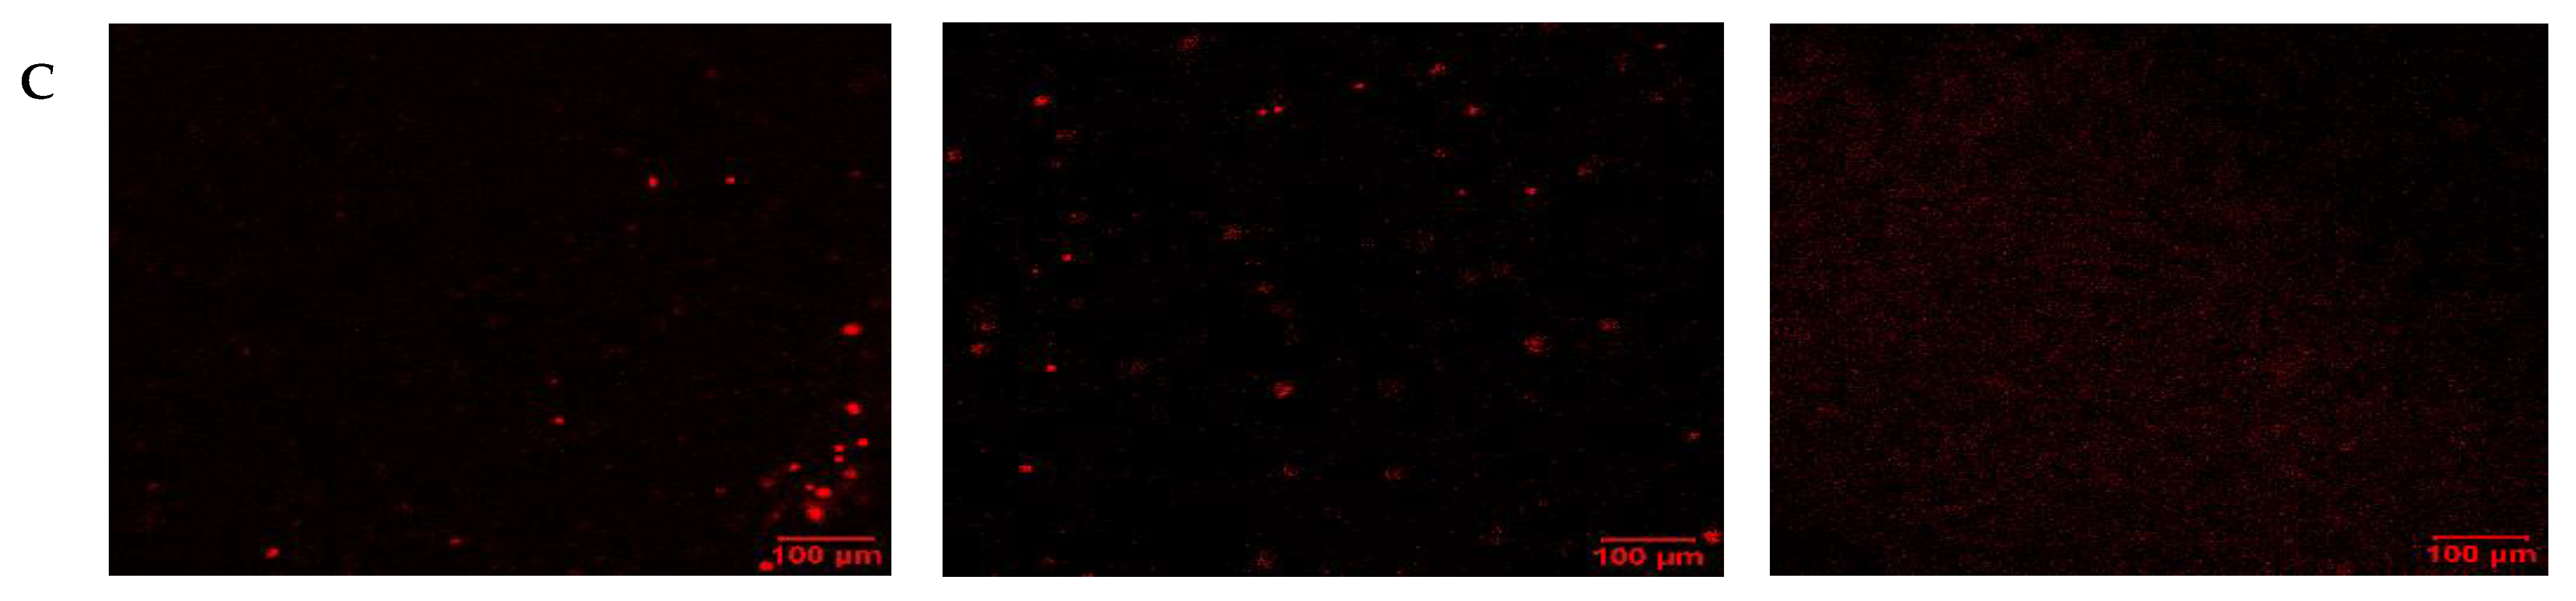

To visualize the apoptotic cells, confocal laser scanning microscopy (LSM) was employed. In this case, single treatments with thymoquinone and carboplatin were compared with untreated control cells. Under normoxic conditions (Figure 6), carboplatin induced very little apoptosis, as evidenced by minimal green staining. Interestingly, with thymoquinone treatment, an absence of nuclear stain and blue stain bleeding into the media was evident. In comparison, under hypoxic conditions (Figure 7), the control showed higher levels of apoptosis and necrosis, reflecting the effect of the harsh hypoxic conditions on untreated cells. Both with carboplatin and thymoquinone treatment, a relatively greater number of cells were seen to be apoptotic, and more were also necrotic compared with the normoxic. Furthermore, with thymoquinone, not all the cells were lysed, as evidenced by the presence of nuclear stain.

Figure 6. Confocal LSM image of OECM-1 cells on treatment with carboplatin, and thymoquinone in normoxic conditions, with nuclear stain (A), apoptotic stain (B) and necrotic stain (C).

Figure 7. Confocal LSM image of OECM-1 cells on treatment with carboplatin, and thymoquinone in hypoxic conditions, with nuclear stain (A), apoptotic stain (B) and necrotic stain (C).